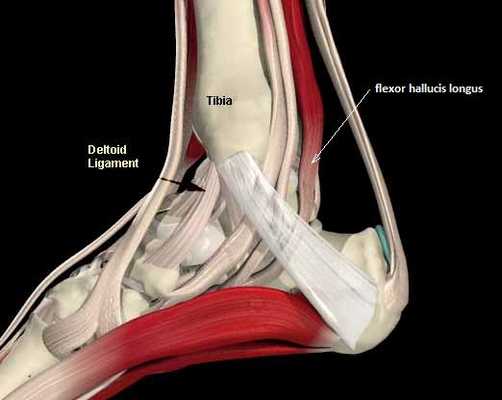

Повреждения сухожилия сгибателя большого пальца стопы распространённый вид травмы в таких группах риска как танцоры (прежде всего балета), гимнасты и скалолазы. Эти группы людей объединяет существенная перегрузка сгибателя большого пальца стопы при выполнении толчков и зацепов, стояния на пуантах. Вторым названием данной патологии является «тендинит танцора». В остальной популяции данные повреждения встречаются крайне редко. Так как сухожилие длинного сгибателя большого пальца проходит в фиброзно-костном канале позади внутренней лодыжки и голеностопного сустава, оно оказывается как бы перекинутым через задний отросток таранной кости, как верёвка перекинутая через блок.

При его хронической травматизации дегенеративные изменения приводят к его утолщению и уплотнению, вызывают его сдавление и ущемление. Может возникнуть так называемый задний импиджмент голеностопного сустава. В случае если в толще сухожилия возникают узелки, может появиться такой симптом как «триггерный палец», когда большой палец согнувшись «защёлкивается», и разогнуть его можно только через боль и приложив значительное усилие. При длительно текущем процессе возможно рубцовое сращение сухожилия со своим каналом, что приводит к псевдо-ригидной деформации первого плюсне-фалангового сустава.

Техника операции при тендините длинного сгибателя большого пальца стопы.

Для хорошей визуализации рекомендуется использование жгута. Выполняется полукруглый разрез параллельно заднему краю внутренней лодыжки. Необходимо аккуратно выделить сосудисто-нервный пучок и взять его на держалку. Доступ к сухожильному каналу можно осуществить как спереди так и сзади по отношению к пучку. На этом этапе возможно выделение сухожилия, после его тщательного осмотра и пальпации, удаляются все узлы, спайки. При обнаружении треугольной кости необходимо её удалить.